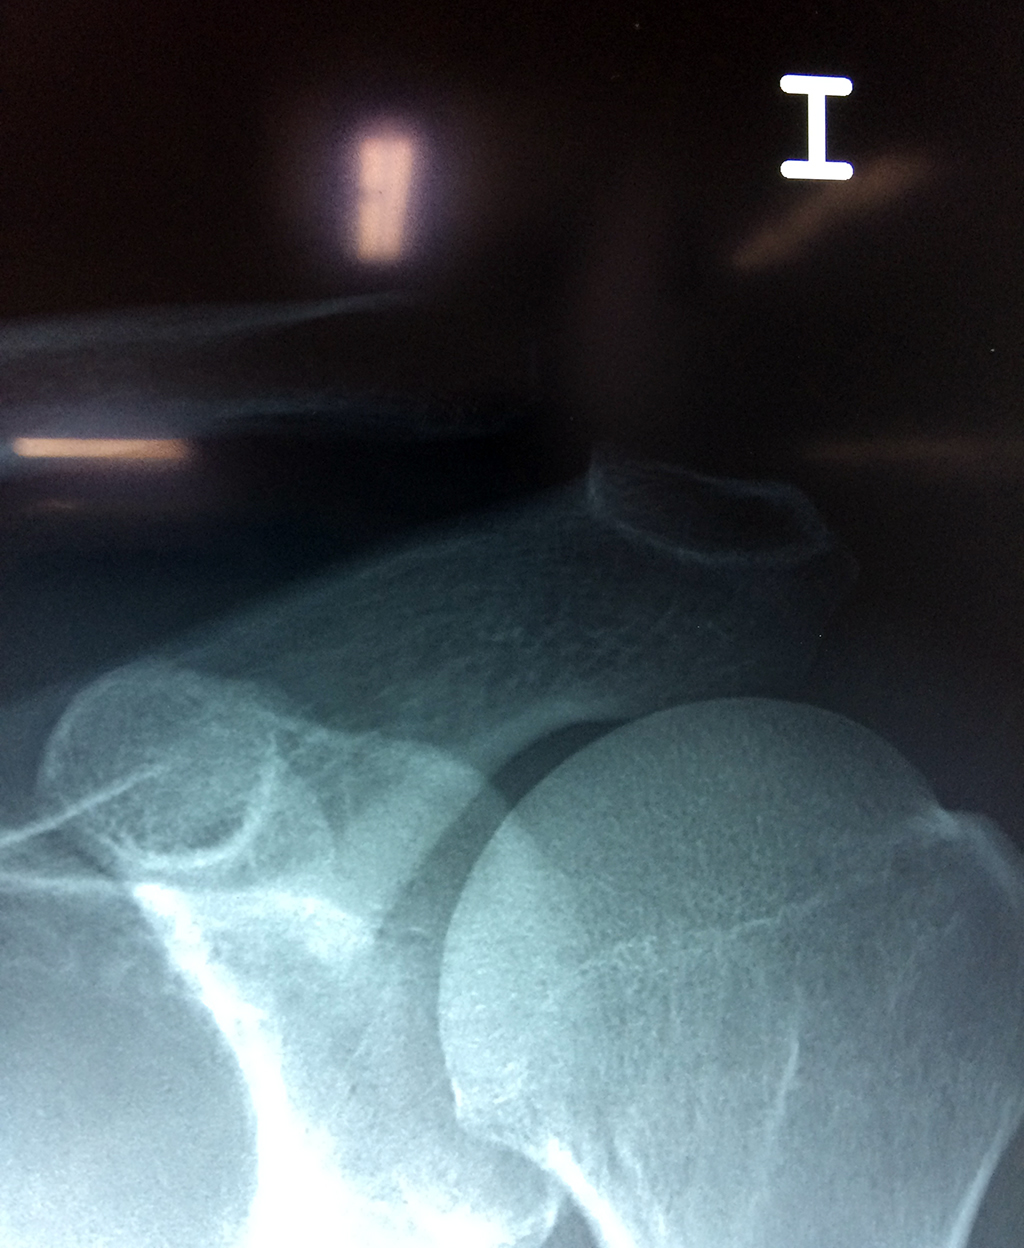

Húmero - Clavícula

La clavícula es un hueso largo, con forma de "S" itálica, situado en la parte anterosuperior del tórax. Junto con la escápula forman la cintura escapular. Se puede palpar por toda su longitud y se extiende del esternón al acromion de la escápula, siguiendo una dirección oblicua lateral y posterior.

Se considera el único medio de unión entre el miembro superior y el tórax. A pesar de su aspecto, similar al de un hueso largo, posee una estructura semejante a la de un hueso plano, ya que carece de epífisis y de diáfisis, lo que la harían entrar dentro de la clasificación de hueso largo. Carece de un canal medular propiamente dicho.